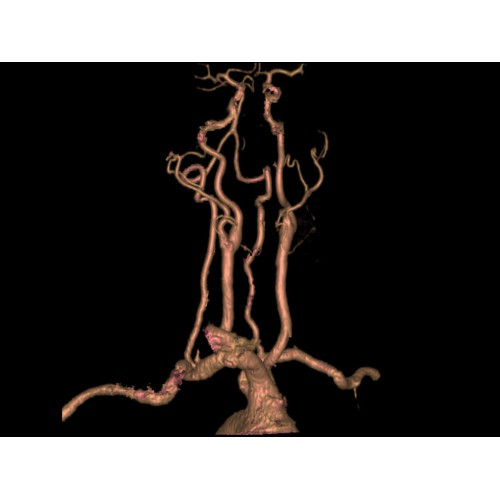

Позволяет проводить комплексные исследования всех анатомических зон, включая нейровизуализацию, ангиографию, исследования органов грудной и брюшной полости. Особенно эффективен для раннего выявления онкологических заболеваний.